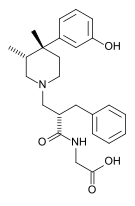

| Opioid peptides | Skeletal molecular images |

|---|---|

| Adrenorphin |  |

| Amidorphin |  |

| Casomorphin | |

| DADLE | |

| DAMGO |  |

| Dermorphin | |

| Endomorphin |  |

| Morphiceptin |  |

| Nociceptin |  |

| Octreotide |  |

| Opiorphin |  |

| TRIMU 5 |  |